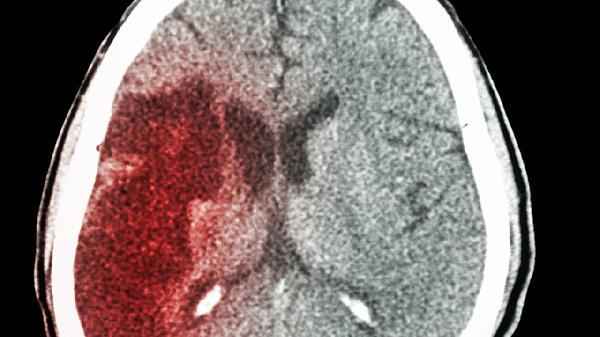

脑安滴丸是一种中成药,主要用于治疗缺血性脑卒中引起的相关症状。

脑安滴丸由川芎、丹参等中药成分组成,具有活血化瘀、改善脑部血液循环的作用。临床上常用于脑卒中恢复期出现的半身不遂、言语不利、肢体麻木等症状。该药物能改善脑部供血,促进神经功能恢复。

主要适用于缺血性脑卒中急性期后的恢复治疗,对因动脉粥样硬化导致脑部血管堵塞的病情具有辅助治疗作用。对于高血压、糖尿病等引起的脑部小血管病变也有一定改善效果。